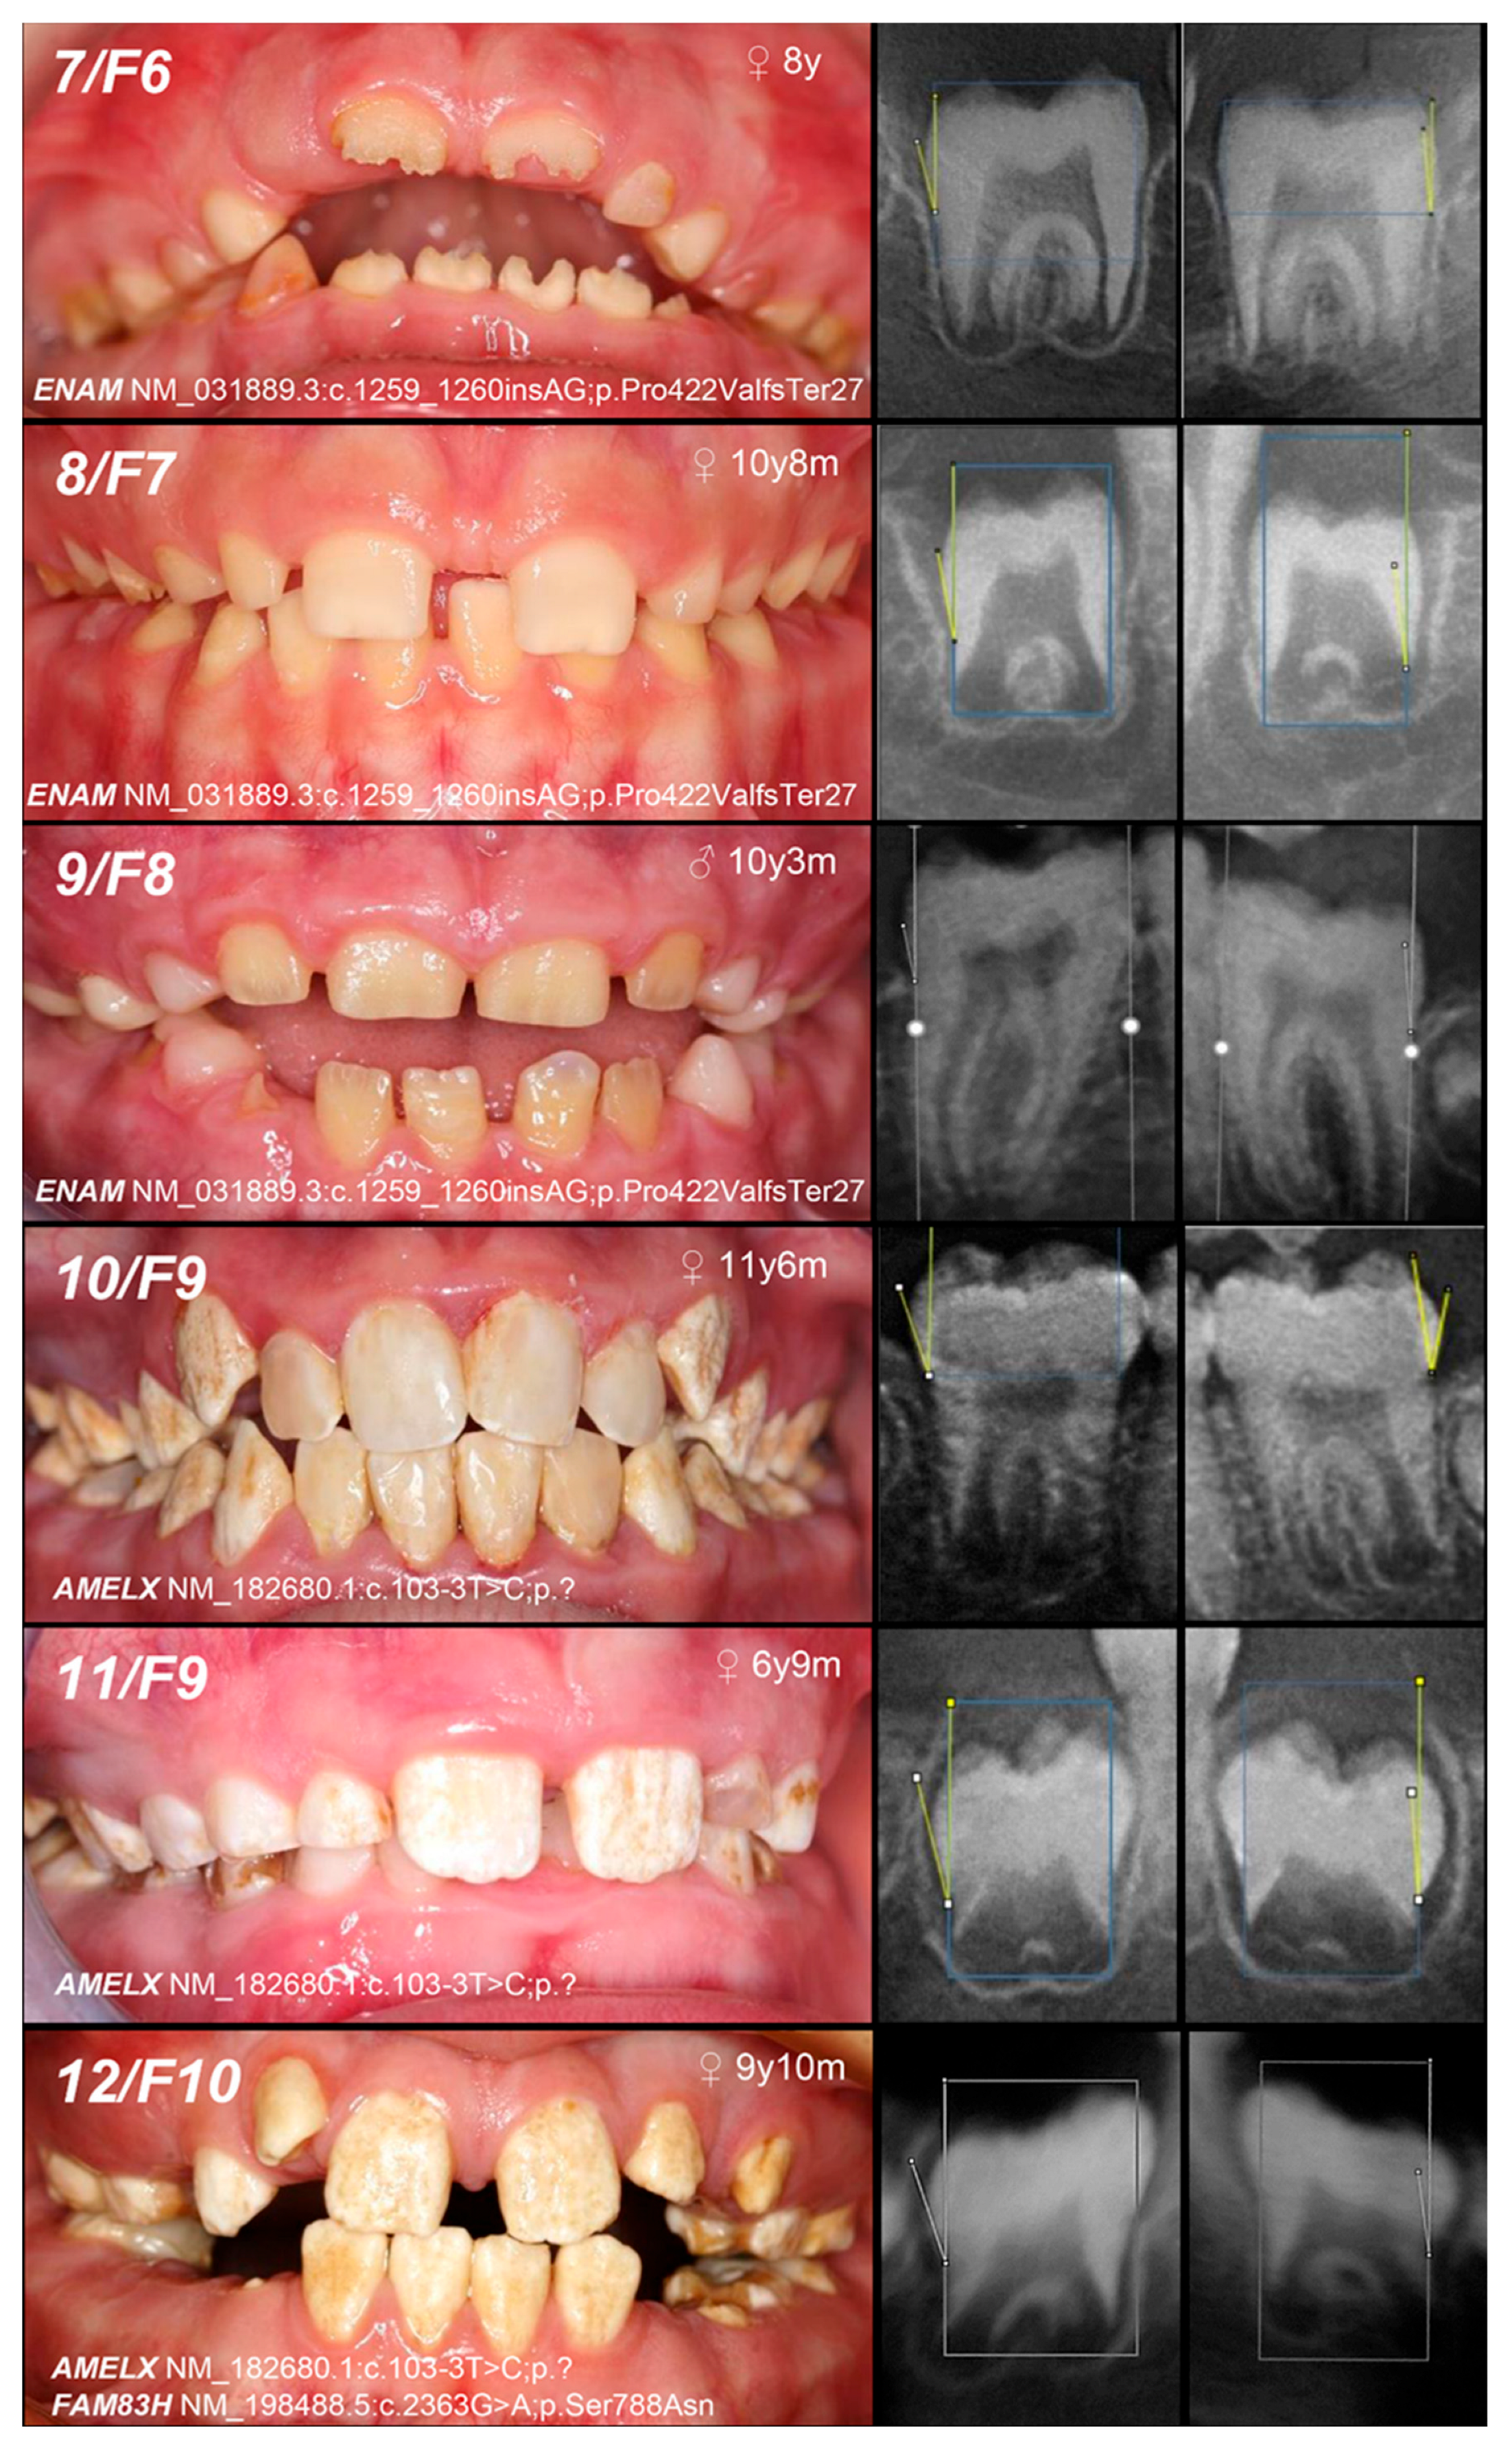

| 7, F6 | MoFaS (UC) | |||||||

| 8, F7 | MoFa (UC) | |||||||

| 9, F8 | MoFa (UC) | |||||||

| 10, 11, F9 | Hypomineralized (heterogeneity) | IE, XLD, AMELX | c.103-3T>C | +/− | p.? | [26] | Mo(U) Fa (AC) | likely pathogenic (PP1:strong, PM2:moderate)* |

| 12, F10 | +/− | Mo (AC) Fa (NA) | ||||||

| and IIIA, AD, FAM83H | c.2363G>A | +/− | p.Ser788Asn | [26] | benign (BA1:stand-alone, BS2:strong, BP4:supporting, BP6:strong) | |||

| 13, F11 | Hypoplastic (heterogeneity) | IE, XLD, AMELX | c.485delT | 0/− | p.Phe162SerfsTer13 | novel | MoS (A) Fa (NA) | likely pathogenic (PVS1:very strong, PM2:moderate) |

| 14, F12 | Hypomineralized (pigmented hypomature) | IIA2, AR, MMP20 | c.389C>T | −/− | p.Thr130Ile | [27] | MoFa (UC) | likely pathogenic (PP5: strong, PM2: moderate) GnomAD: 0.001747 |

| 15, F13 | +/− | Mo (U) Fa (NA) | ||||||

| and c.446G>A | +/− | and p.Trp149Ter | novel | likely pathogenic (PVS1:very strong, PM2:moderate) GnomAD: 0.00000398 |

| 16, F14 | Hypomineralized (pigmented hypomature) | IIA2, AR, MMP20 | c.540T>A | +/− | p.Tyr180Ter | [28] | Mo (UC) Fa (U) | likely pathogenic (PVS1: very strong, PM2: moderate) GnomAD: 0.00000707 |

| 17, 18, F15 | c.811G>T | +/− | p.Gly271Ter | novel | Mo (AC) Fa (U) | likely pathogenic (PVS1: very strong, PM2: moderate) | ||

| +/− | ||||||||

| 19, F16 | +/− | Mo (UC) Fa (U) | ||||||